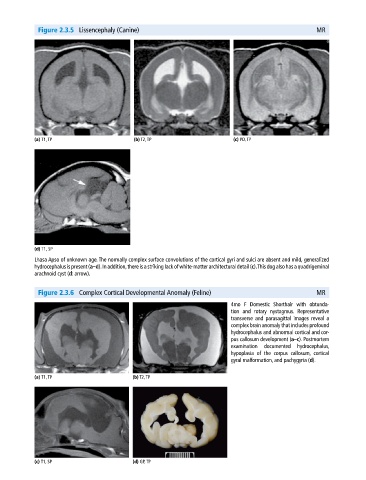

Figure 2.3.5 Lissencephaly (Canine) MR

(a) T1, TP (b) T2, TP (c) PD, TP

(d) T1, SP

Lhasa Apso of unknown age. The normally complex surface convolutions of the cortical gyri and sulci are absent and mild, generalized

hydrocephalus is present (a–d). In addition, there is a striking lack of white‐matter architectural detail (c). This dog also has a quadrigeminal

arachnoid cyst (d: arrow).

Figure 2.3.6 Complex Cortical Developmental Anomaly (Feline) MR

4mo F Domestic Shorthair with obtunda-

tion and rotary nystagmus. Representative

transverse and parasagittal images reveal a

complex brain anomaly that includes profound

hydrocephalus and abnormal cortical and cor-

pus callosum development (a–c). Postmortem

examination documented hydrocephalus,

hypoplasia of the corpus callosum, cortical

gyral malformation, and pachygyria (d).

(a) T1, TP (b) T2, TP

(c) T1, SP (d) GP, TP